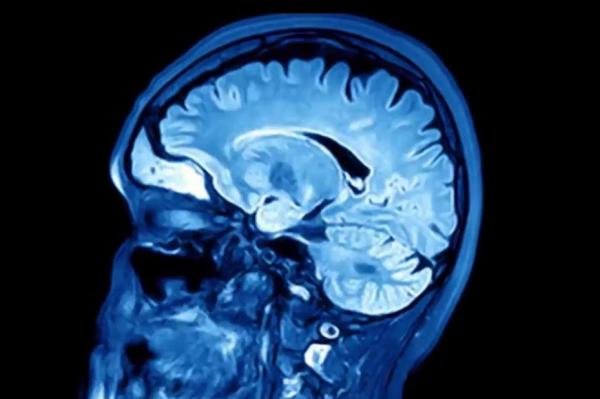

اکنون در آستانه همهگیری بیماری دیگری هستیم؛ بیماری که سیستم ایمنی بدن را هدف قرار نمیدهد بلکه مغز، حافظه و شخصیت انسان را تهدید میکند.